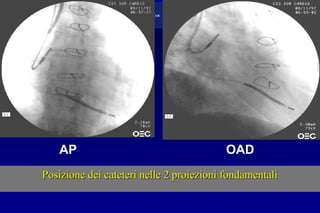

Posizione dei cateteri nelle 2 proiezioni fondamentaliPosizione dei cateteri nelle 2 proiezioni fondamentali

AP OAD

Posizione dei cateterinelle 2 proiezioni fondamentaliPosizione dei cateteri nelle 2 proiezioni fondamentali AP OAD